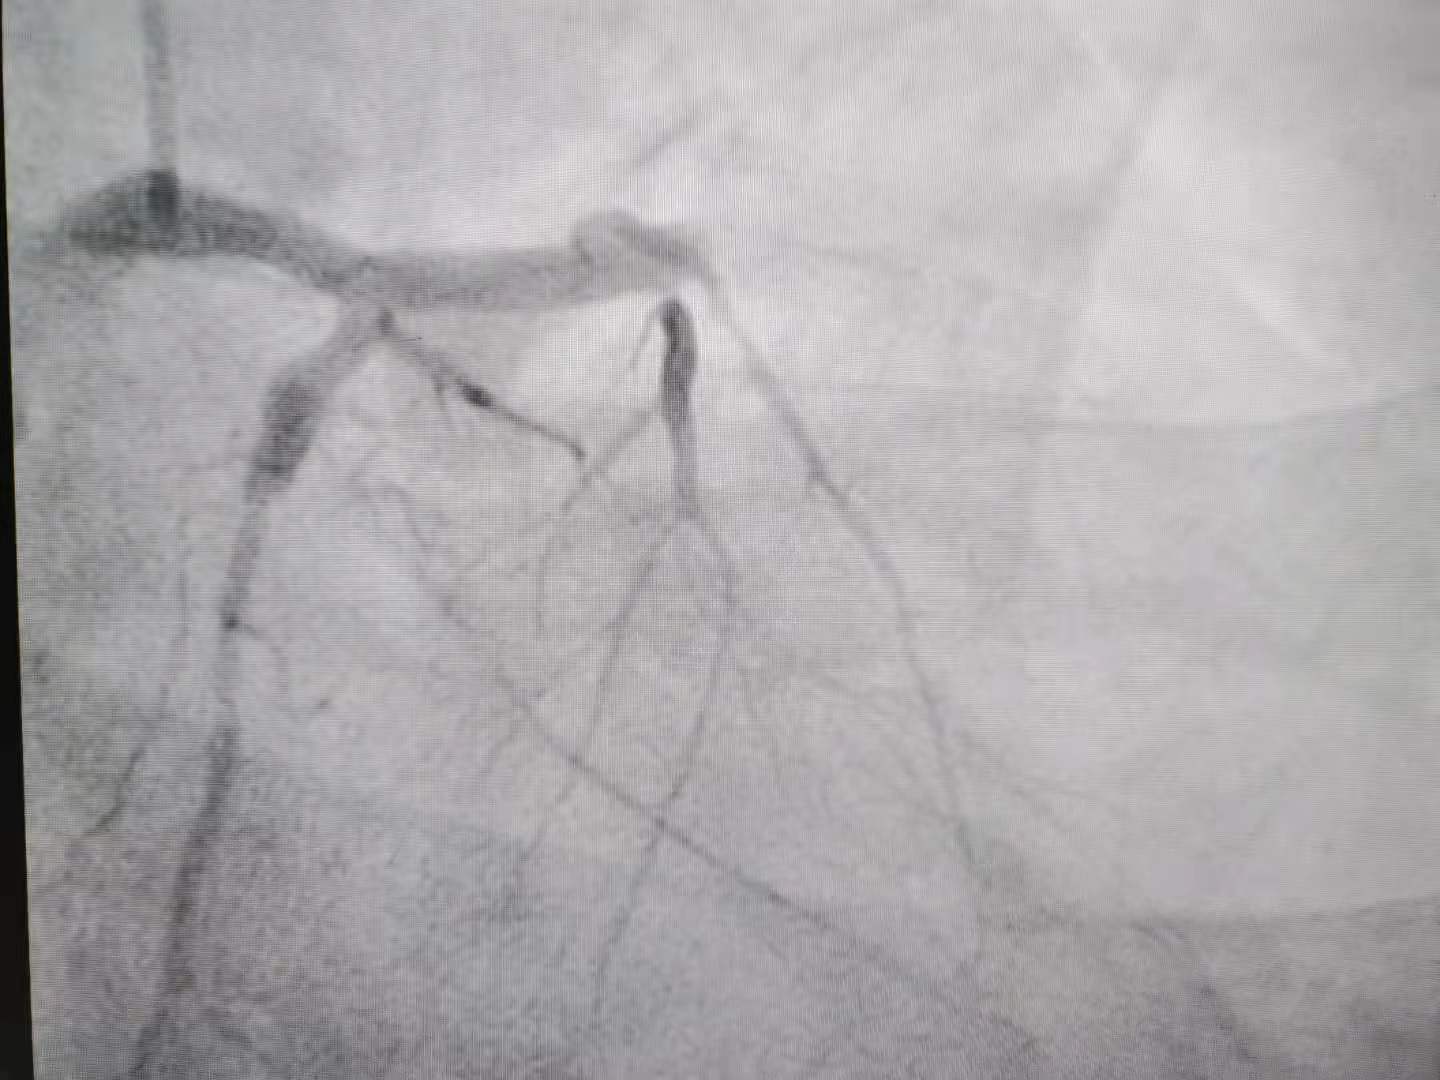

经过手术,血管成功开通。上:血管开通前,下:血管开通后。